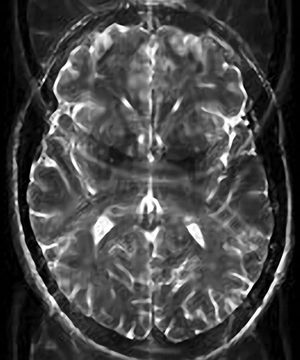

T2-w Single-Shot Echo Planar Imaging (SS-EPI) sequence. Nyquist (N/2) ghost or "three brains" artifact.